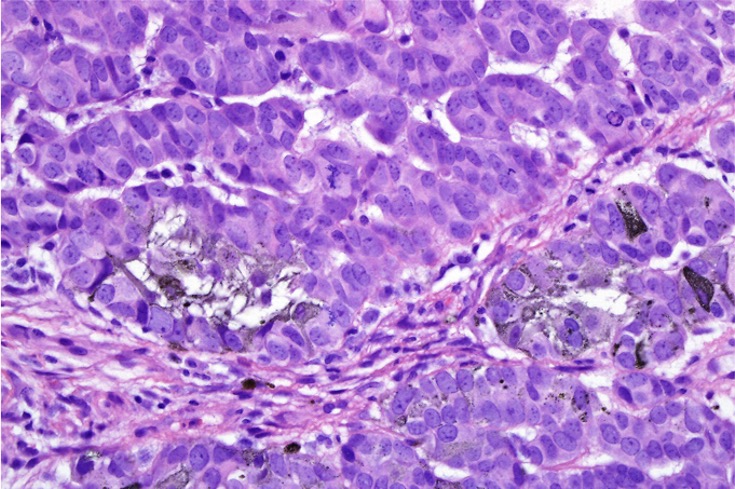

This is a very rare tumor with only 31 cases documented in the literature. It consists of an admixture of matricial cells & usually, heavily pigmented dendritic cells although in some cases, eithelioid melanocytes may also be present.

•Heavily pigmented dendritic +/- epithelioid melanocytes

•Dendritic population is enhanced with a Masson Fontana stain